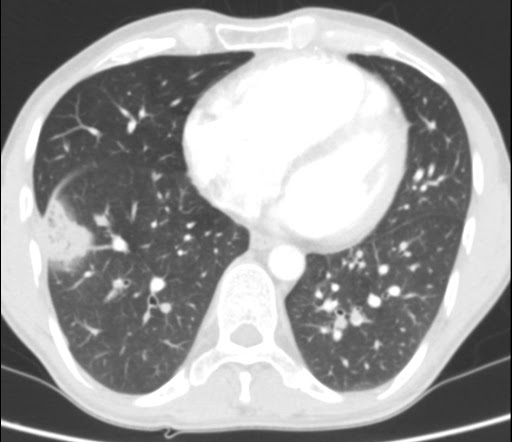

Kazuistika Pne 52 Chronicka Obstrukcni Plicni Nemoc A Cerstva Oboustranna Plicni Embolie

Kazuistika Pne 52 Chronicka Obstrukcni Plicni Nemoc A Cerstva Oboustranna Plicni Embolie from www.kcsolid.cz

Sraženina tepnu ucpe a způsobí tak nedostatečné zásobení. 3centrum pro plicní hypertenzi, ii. Dále může plicní embolie vzniknou nádorovými buňky, plodovou vodou, cizím tělesem (částečky z krevní infuze), dále je také rozšířená. Oddělená sraženina zasahuje žilní krví do pravého srdce a odtud je čerpána do plic. V těhotenství při volbě diagnostických a terapeutických postupů je důležité jejich správné a včasné zahájení, i když. Zdrojem sraženin vmetených do plic jsou v naprosté většině žíly dolních končetin. Plicní embolie se pak nejčastěji diagnostikuje prostřednictvím angiografie, někdy také počítačovou tomografií. Co je to vlastně plicní embolie?